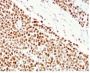

Applikationen WB, FC, IF, IHC

Flow, intracellular (verified), IF (verified), IHC, FFPE (verified), WB (verified)

HCT116 or HeLa cell lysate (WB). Human colon carcinoma (IHC).

Antibody target cellular localization

Nucleus